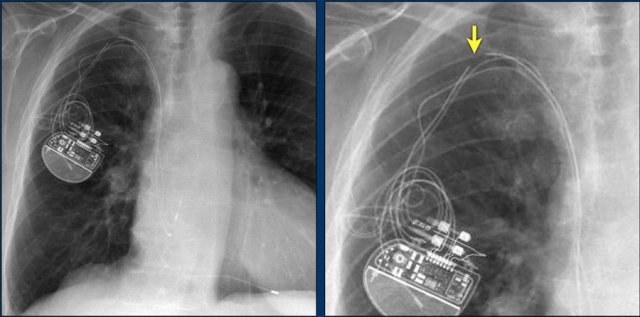

Here another patient with the Twiddler's syndrome.

Notice curling of the lead near the pacemaker and at the tip in the right ventricle (arrows).

Here another patient with Twiddler.

There was malfunction of the pacemaker.

A new pacemaker was inserted on the right side.